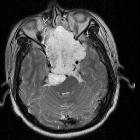

MRI

- T1

- intermediate to low-signal intensity

- small foci of hyperintensity (intratumoral hemorrhage or a mucus pool)

- T2: most exhibit very high signal

- T1 C+ (Gd)

- heterogeneous enhancement with a honeycomb appearance corresponding to low T1 signal areas within the tumor

- greater enhancement has been associated with poorer prognosis

- SWI/GE: variable intralesional hemorrhage, suggested by the presence of blooming artefact